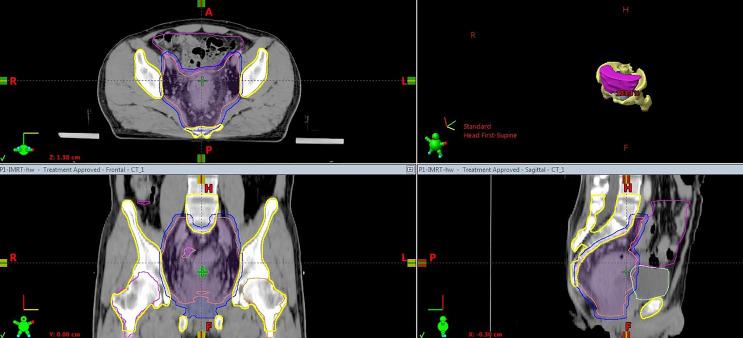

Effect of Pelvic Bone Marrow Sparing Intensity Modulated Radiation Therapy on Acute Hematologic Toxicity in Rectal Cancer Patients Undergoing Chemo-Radiotherapy.

112 rectal cancer patients were selected and divided into the PBM sparing IMRT group (60 cases) and the non-PBM sparing IMRT group (52 cases). All patients underwent pelvic radiotherapy with concurrent capecitabine-based chemotherapy. The PBM dosimetric constraints in the PBM sparing IMRT group were set to:V ≤ 85%, V ≤ 65% and V ≤ 45%. An independent sample t test was applied for the dose-volume parameters, and Chi-squared analysis was applied for clinical parameters and adverse events.

The radiation dose to PBM (VV, D, <0.05), PBM sub-regions (VV, D, <0.05) and both femoral heads (V~V, D, <0.05) decreased significantly in the PBM sparing IMRT group compared with that of the non-PBM sparing IMRT group (<0.05). There was no significant difference in any dose-volume parameters of the bladder and small bowel in either groups, and none in the planning target volume (PTV) dose homogeneity and conformity (>0.05). For acute HT observation, the incidence of grade 3 acute HT (χ = 7.094, =0.008) was significantly reduced in patients treated with PBM sparing IMRT compared with patients treated with non-PBM sparing IMRT. There was no statistical difference in the incidence of vomiting, diarrhea, fatigue, anorexia, nausea, hand-foot syndrome, cystitis, perianal pain and perianal dermatitis in patients of both groups (0.05).

Applying PBM dosimetric constraints (V ≤ 85%, V ≤ 65% and V ≤ 45%) can significantly reduce the radiation dose to PBM. The patients treated with PBM sparing IMRT had a lower incidence of acute HT compared with those treated with non-PBM sparing IMRT. Applying the PBM dosimetric constraints proposed by our study can benefits the patients with rectal cancer undergoing capecitabine-based chemo-radiotherapy.